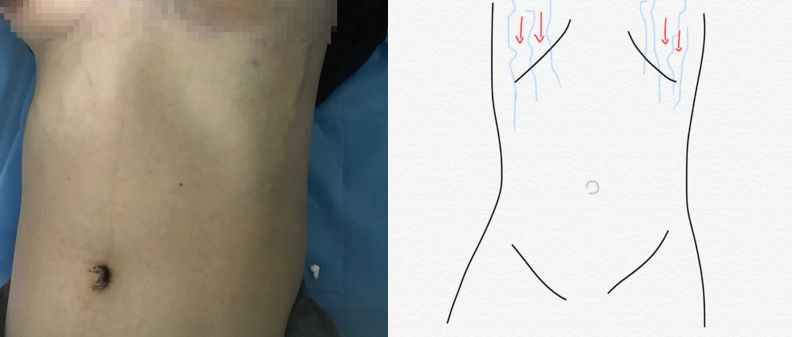

上腔静脉阻塞伴侧枝循环形成时:

上腹壁或胸壁的浅静脉曲张。曲张浅静脉的血流方向均转向下。

因为进行体格检查时发现病人对称性的双侧上腹壁浅静脉曲张,遂继续检查双侧颈静脉、锁骨下静脉及头臂静脉。

体格检查如图: